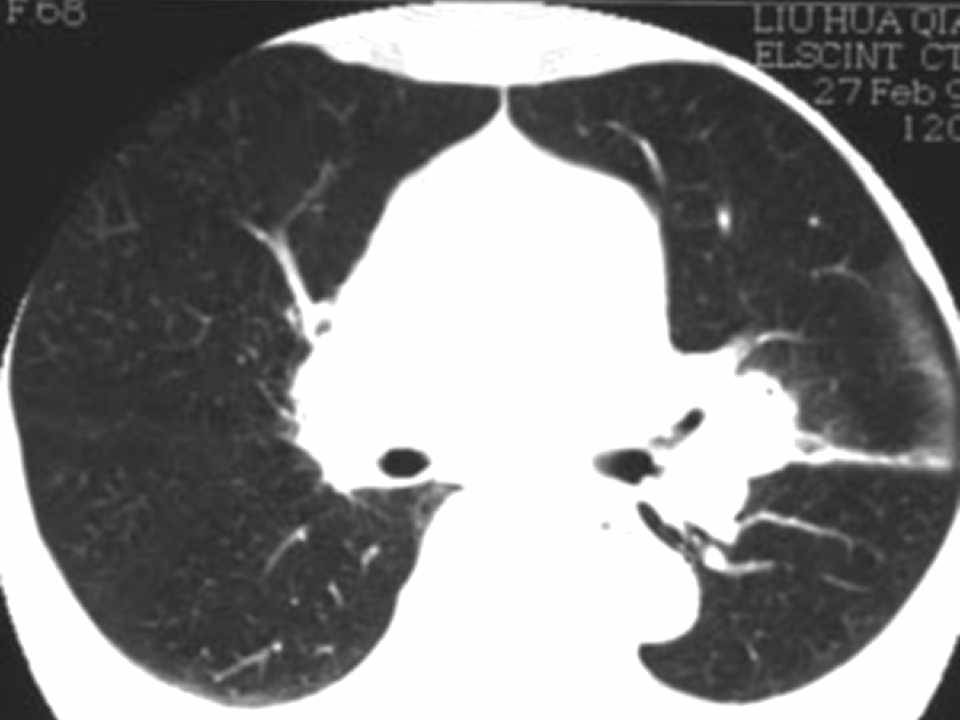

肺癌影像学表现